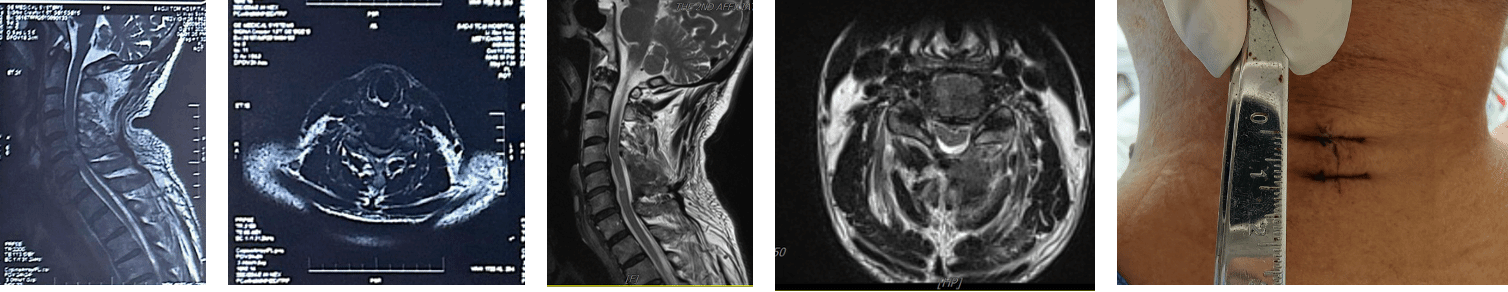

据了解,患者因左手麻木、行走不稳等症状在外院就诊,行颈椎MRI检查提示:颈3/4、颈6/7椎间盘变性并膨出,颈4/5椎间盘变性并突出(中央型),颈5/6椎间盘变性膨出并突出(中央偏左型),颈5/6层面椎管狭窄,脊髓受压、变性,腰3/4椎间盘变性并膨出,建议行颈前路椎管减压植骨融合内固定术等传统开放手术。患者由于对手术创伤、内植物等方面存在顾虑,多方打听后得知我院李锋涛教授在脊柱微创领域造诣深厚、经验丰富,遂慕名前来寻求进一步治疗。

入院后,在王栋主任指导下,李锋涛教授带领团队对患者的病情进行全面细致的评估,结合影像学检查结果和患者的身体状况,反复研讨后制定了个性化的手术方案—UNSES/AUSS技术下颈椎多节段单侧入路双侧减压术。该手术方式相较于传统手术,具有创伤小、恢复快、无需放置内植物等显著优势,能在精准解除脊髓压迫的同时,最大程度减少对周围组织的损伤。术后患者症状明显好转,术后复查影像学显示受压脊髓获得充分减压。仅1.5厘米的手术伤口愈合顺利,相较于传统手术大幅缩小的创伤,让恢复过程更加轻松。术后第二天,患者便能自主下地活动,左手麻木、行走不稳的困扰显著缓解,精神状态焕然一新。

1.5厘米的伤口与脊髓压迫的充分解除,直观展现了脊柱微创技术的精准与高效。此次手术的成功开展,不仅充分彰显了我院在脊柱微创领域的技术实力和诊疗水平,也为更多颈椎病变患者带来了福音。